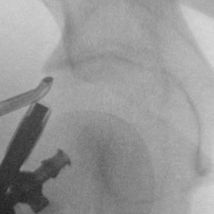

Hip arthroscopy, also referred to as "keyhole" or minimally invasive hip surgery, is typically necessary for hip pain that does not improve with conservative treatment. Small incisions are made only big enough to place a small video camera and specialized instruments into the hip joint, trochanteric space, and/or ischial space to clearly diagnose and treat hip pathology.

- Femoroacetabular Impingement (FAI) - Cam deformity; Pincer deformity

Click on a hip condition below to see the repair.